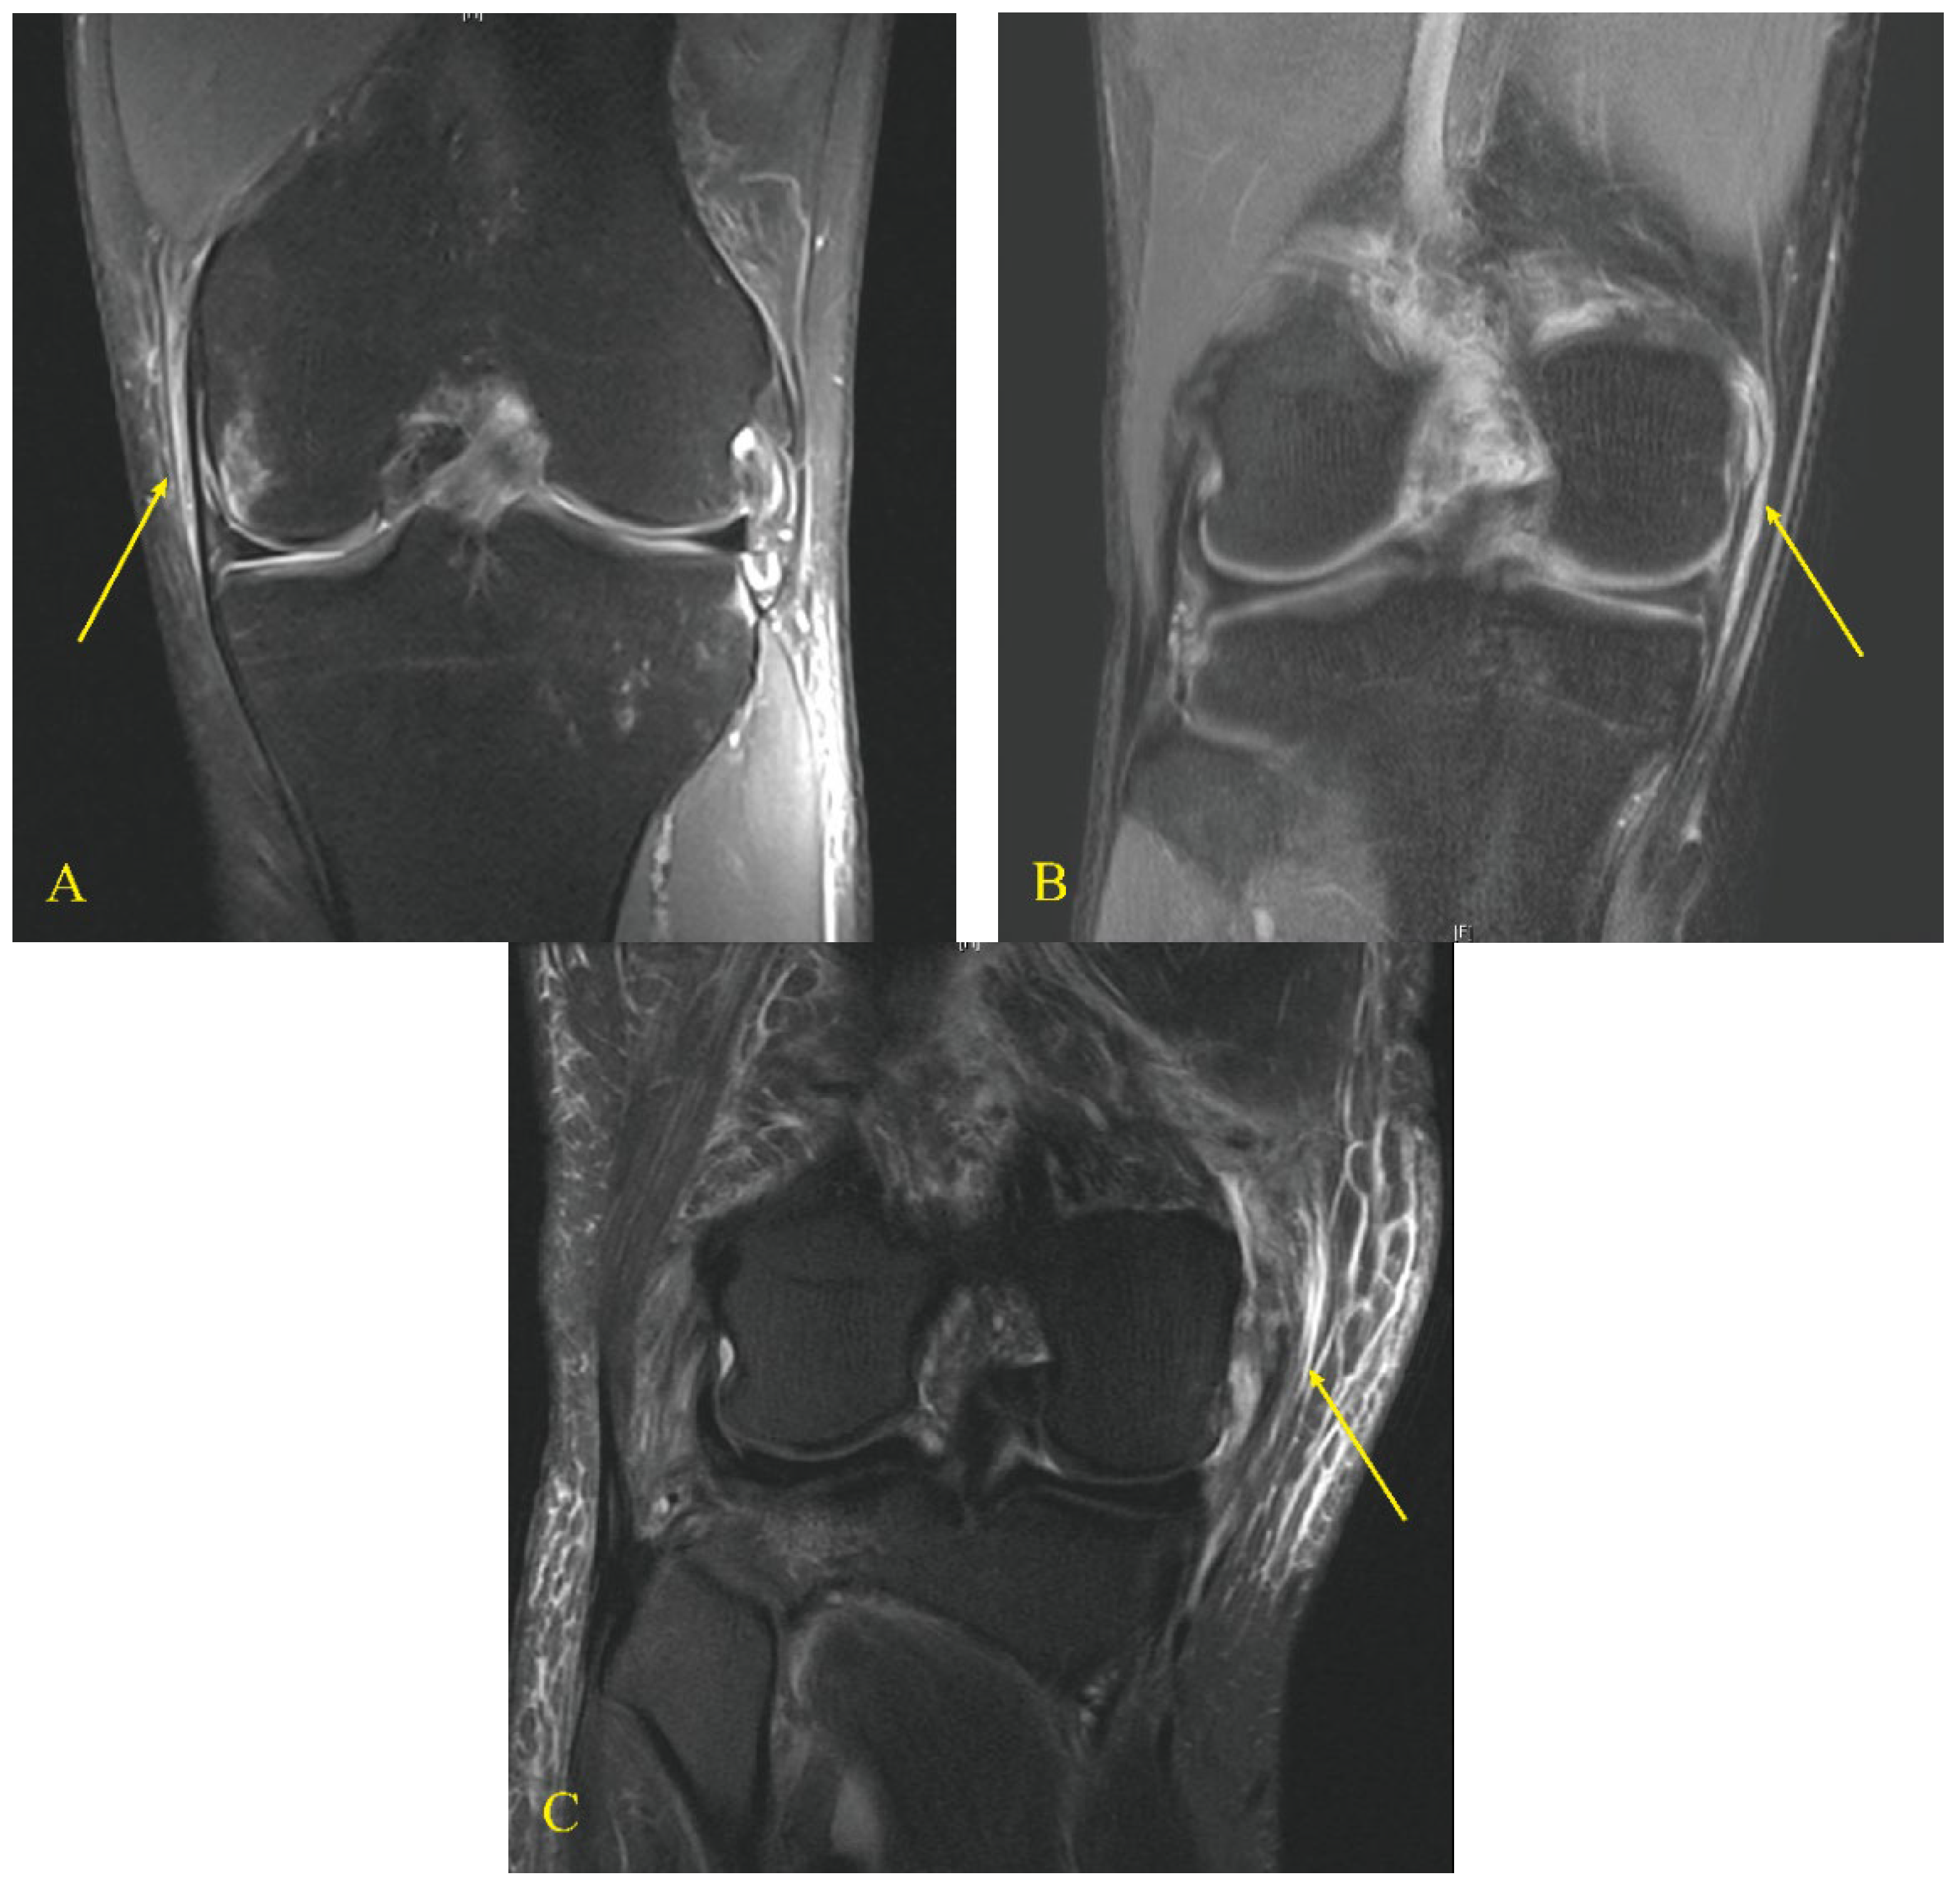

A total of 1187 patients underwent autologous ACL reconstruction during the study period. Of these, 169 patients were included in the study (Figure 1). As per the graft type used in ACL reconstruction, the patients were divided into two groups: group B, ACL reconstruction using a BPTB graft (n = 92) and group H, ACL reconstruction using quadrupled hamstring graft (n = 77). Each group was subclassified according to the grade of MCL injury on magnetic resonance imaging (MRI) scans [27]: grade I included peri-ligamentous edema around the MCL on fluid-sensitive sequences; grade II included partial disruption of the ligamentous structures; and grade III included complete disruption of the superficial and deep MCL (Figure 2) [27].

Figure 2.

Grades of MCL injury on magnetic resonance imaging scans. Grade I (A) peri-ligamentous edema around the MCL on fluid-sensitive sequences, grade II (B) partial disruption of the ligamentous structures, and grade III (C) complete disruption of the superficial and deep MCL. Yellow arrows indicate the torn MCL based on the grade.